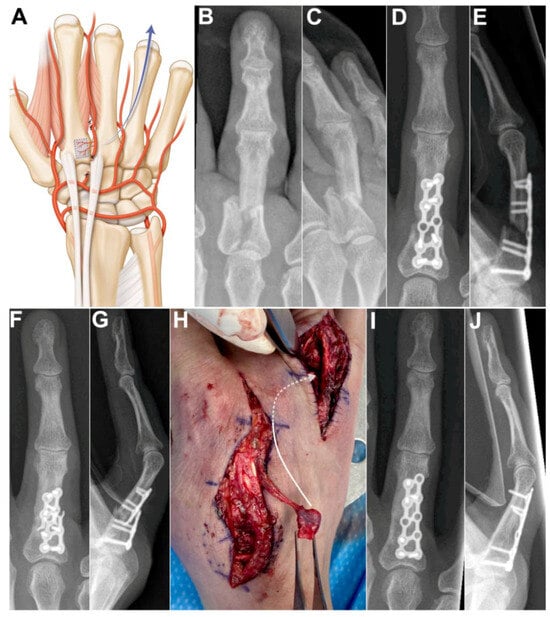

Case 4: A 53-year-old female presented with nonunion of the ring finger proximal phalanx seven months after an osteosynthesis with a dorsal plate and screws. The absence of bone healing led to hardware failure. A longitudinal incision was made over the 2nd metacarpal and another longitudinal incision over the first phalanx of the 4th ray. After bone debridement, a 1 cm gap remained between the bone stumps. The 2DMA was ligated proximally to the base of the second metacarpal. The proximal anastomosis with the deep palmar artery was ligated (Figure 5A). The 2DMA flap was pedicled distally on the distal penetrating branch of the deep palmar artery. Gentle dissection between extensor tendons and skin was made to allow passage of the vascularized 2nd metacarpal-base bone graft to the 4th ray. The size of the pedicled bone was 0.9 × 0.9 cm. A new plate and screws (Aptus, Medartis, Switzerland) provided stability. We witnessed bone union after ten weeks (Figure 5B–E). The patient was free of pain and recovered excellent grip strength (27 kg on the right hand and 30 kg on the left hand), and the range of motion (flexion/extension) was 75/25 degrees for the metacarpophalangeal joint, 55/−10 degrees for the proximal interphalangeal joint and 50/0 degrees for the distal interphalangeal joint of the finger. No complications were observed at the donor and recipient sites. Clinical and radiological outcomes were unchanged 2 years after surgery.

Figure 5. (A) Arterial anatomy, the distally based flap requires ligating the 2DMA proximally to the base of the second metacarpal as well as the palmar communicating branch; Case 4. (B,C) preoperative X-rays showing unstable and displaced intra-articular fracture of the first phalanx of the 4th ray. (D,E) postoperative X-rays, osteosynthesis with a dorsal plate and screws. (F,G) 7 months after osteosynthesis, X-rays showing unstable nonunion of the proximal phalanx after plate breakage; (H) Intraoperative photograph showing vascularized bone graft, dissection between extensor tendons and skin was made to allow passage of the vascularized 2nd metacarpal-base bone graft to the 4th ray (arrow). (I,J) postoperative X-rays demonstrating union of the phalanx.